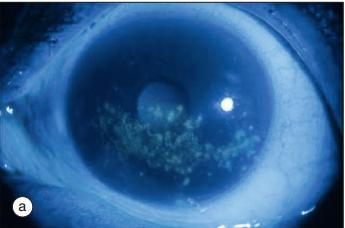

- 眼干症状:眼部刺激感、砂砾感、异物感、内眦堆积有稠厚的绳状物(黏液丝)等。常在夜间加重;然而却可以因哭泣而流眼泪。

丽莎胺绿染色见点状角膜损伤

丽莎胺绿染色见三角形的角膜损伤